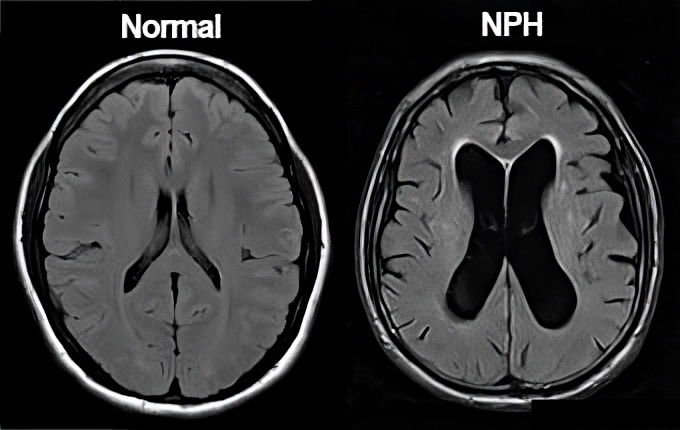

Hình 1. Hình ảnh MRI mặt phẳng cắt ngang với hình ảnh não thất bình thường (A) và não thất giãn lớn (B)

Chụp MRI não: cho thấy giãn não thất không tương xứng với độ teo não, đặc biệt chỉ số Evans > 0,3.